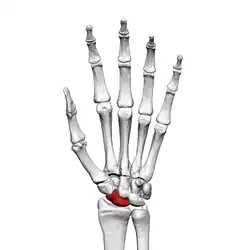

![]() Left hand anterior view (palmar view). Scaphoid bone shown in red. | |

The scaphoid bone is one of the carpal bones of the wrist. It is situated between the hand and forearm on the thumb side of the wrist (also called the lateral or radial side). It forms the radial border of the carpal tunnel. The scaphoid bone is the largest bone of the proximal row of wrist bones, its long axis being from above downward, lateralward, and forward. It is approximately the size and shape of a medium cashew nut.

The scaphoid is situated between the proximal and distal rows of carpal bones. It is located on the radial side of the wrist,[1]: 176 adjacent to the styloid process of the radius.[2] It articulates with the radius, lunate, trapezoid, trapezium, and capitate.[1]: 176 Over 80% of the bone is covered in articular cartilage.[3]